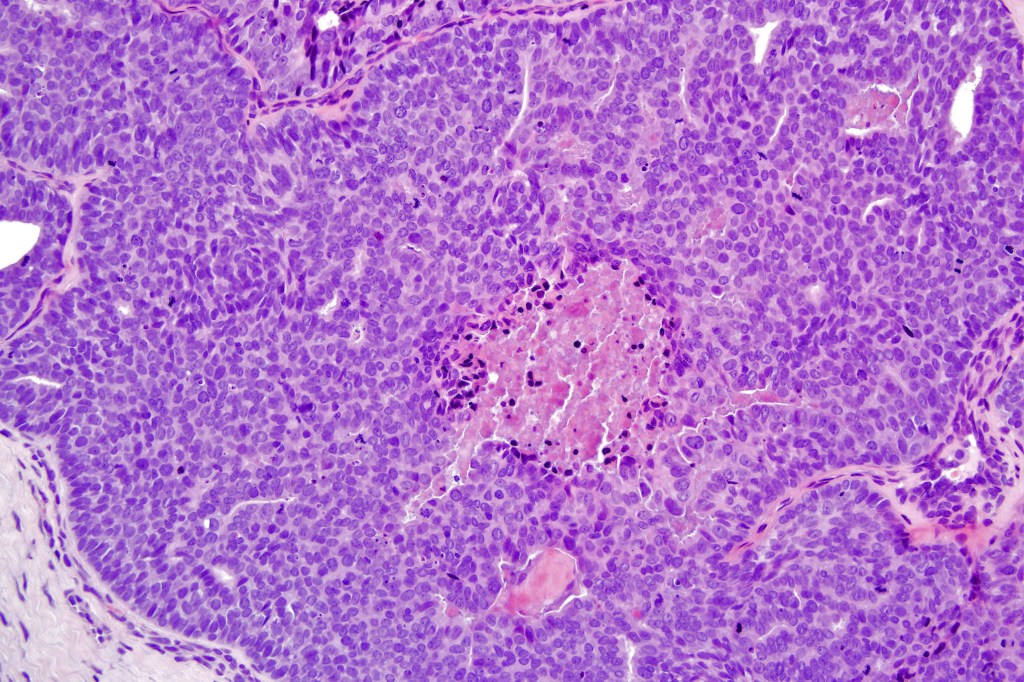

Histological features

•Frequently circumscribed solid/cystic dermal nodule, infiltrative margin rare

•Papillary component (may include pseuopapillae & true papillae with a fibrovascular core)

•Back-to-back glands with double-layered epithelium

•Cuboidal/columnar with eosinophilic cytoplasm & vesicular nuclei

•Variable pleomorphism & mitotic activity (can appear deceptively bland)

•Often dense, hyalinized collagenous stroma